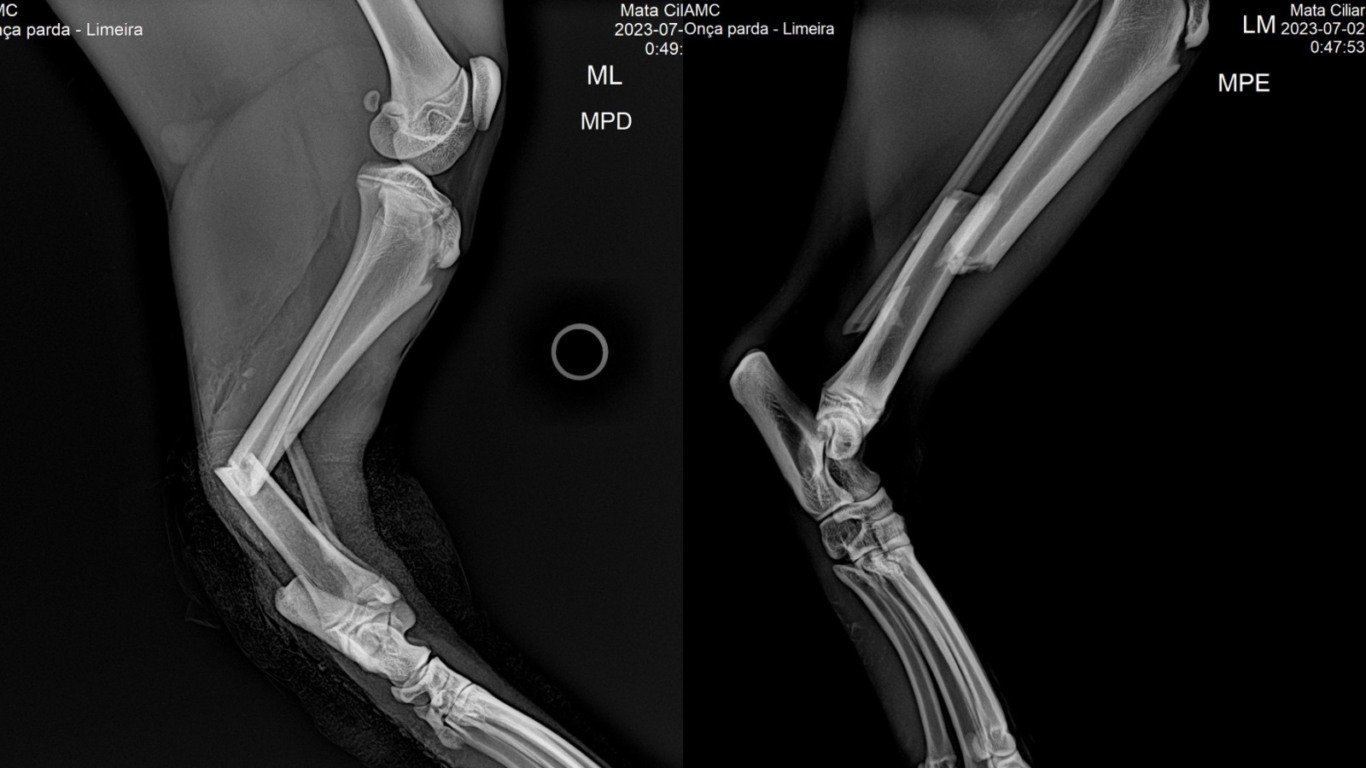

A equipe da Mata Ciliar anestesiou a onça a distância e, em seguida, trouxe o felino para o Cras em Jundiaí. Aqui, o animal passou por exames e radiografia que identificou fraturas múltiplas nas duas patas traseiras. O animal deverá passar por cirurgia nos próximos dias e está sob os cuidados da associação.